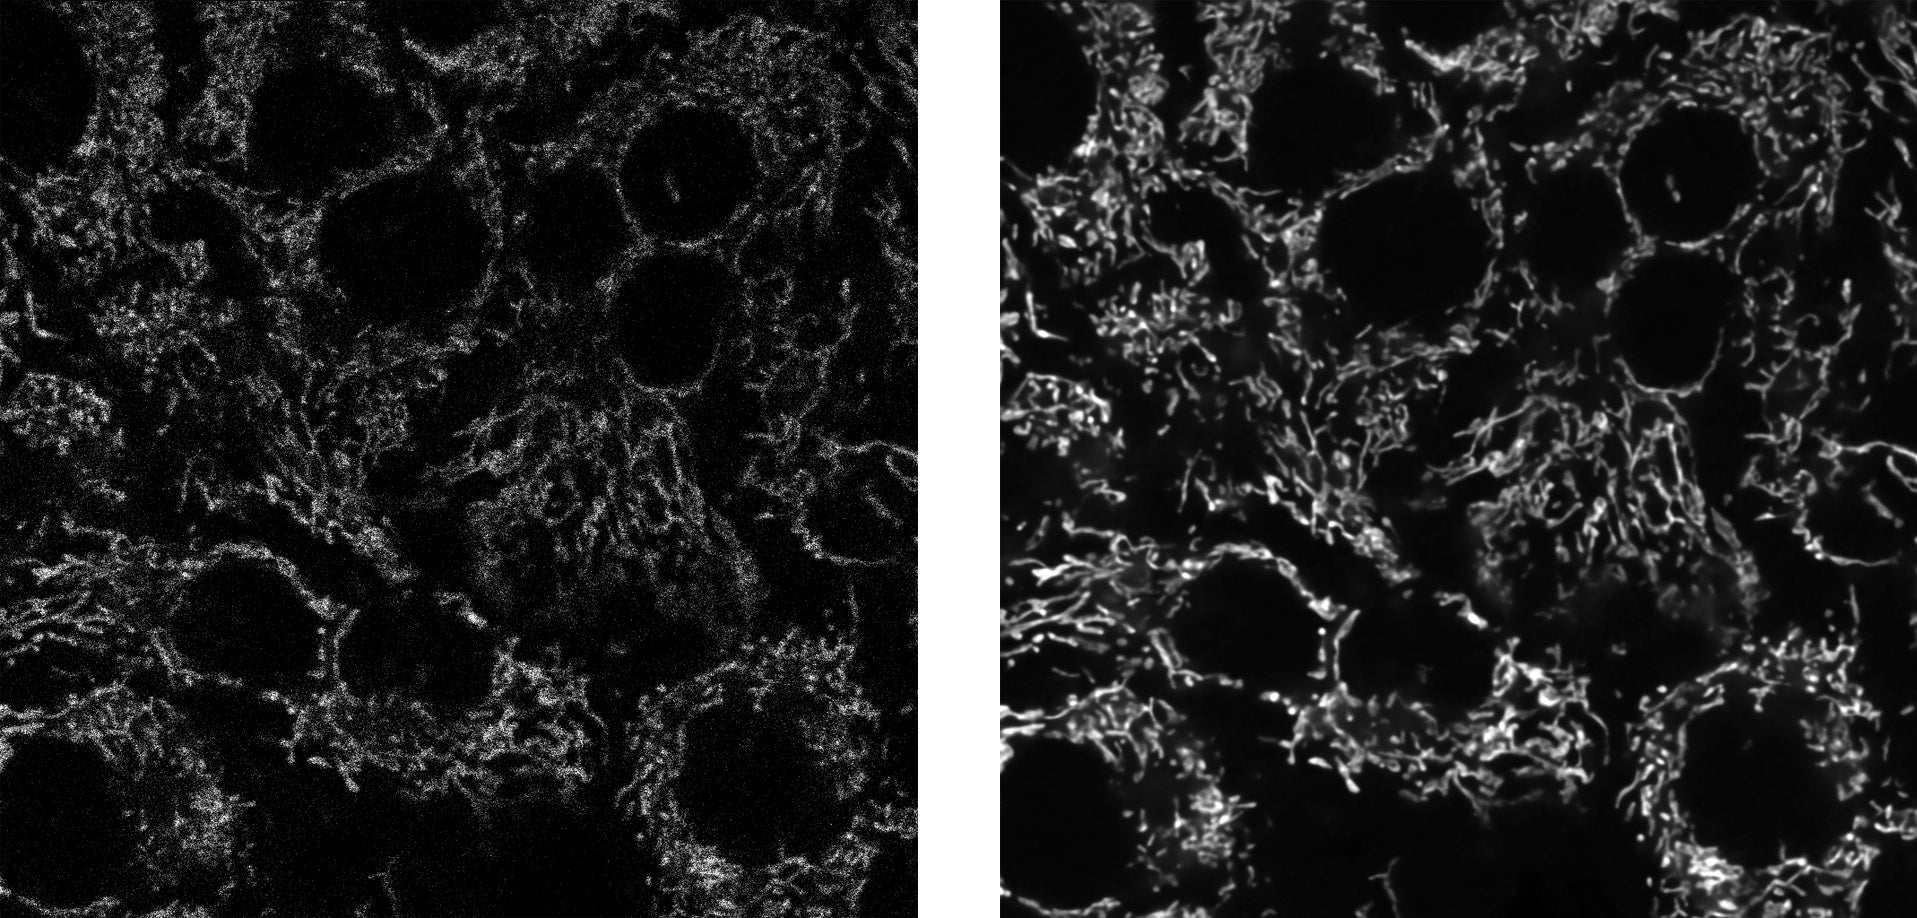

左:従来機種で撮影した画像、右:「SilVIR」を搭載した「FV4000」で撮影した画像

脳神経、がん、免疫の研究では、細胞内部の微細な構造を立体的に観察することが求められています。本製品はシリコン光増倍器(SiPM)と独自の信号処理技術を組み合わせた新開発の検出器「SilVIR」を搭載し、高S/N比で、広いダイナミックレンジの画像を、煩雑な調整を必要とすることなく取得できます。これにより、再現性のある安定した実験に貢献します。